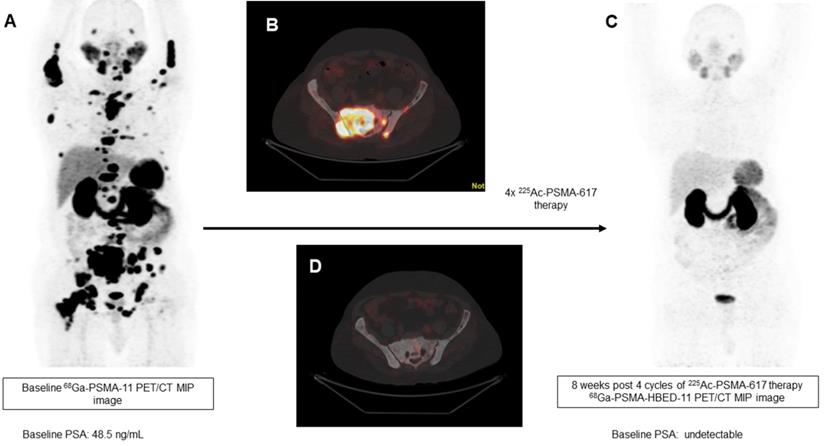

In our patient series, 2 patients achieved clinical, biochemical, and molecular complete remission. In the first patient, a remarkable complete resolution of disease was noted, who was heavily pretreated with standard therapies including 177Lu-PSMA-617 RLT. After receiving 4 cycles of fixed-dose 100 KBq/KgBW 225Ac-PSMA-617 therapy, no grade III/IV toxicities were documented, but the patient experienced fatigue and dry mouth as the main side-effects (Figure 7). The complete molecular and biochemical response was observed in the second patient, in whom the disease was limited to the primary and lymph nodes (Figure 8). This patient received a fixed dose of 100 KBq/KgBW/cycle for 7 cycles. After first two initial cycles of 225Ac-PSMA-617 therapy, 68Ga-PSMA PET/CT scan demonstrated a significant reduction in the cancer burden, revealed residual disease in the mediastinal lymph nodes with fluctuating PSA, hence, further 5 cycles were required to achieve complete biochemical, molecular and morphological response. During the entire treatment course and the follow-up duration, hematological, kidney, and hepatotoxicity were limited to grade I/II. The patient experienced moderate fatigue, which was transient and reduced approximately after 1 week of each cycle of 225Ac-PSMA-617 TAT. The onset of dry mouth symptoms occurred after the 2nd cycle of therapy, which was persistent throughout the follow-up and was grade I/II. At the time of manuscript writing, both the patients are surviving and in complete remission.

Figure 7

A 79-year-old prostate cancer patient treated with hormonal and chemotherapy and refractory to prior 177Lu-PSMA-617 presented with radiotracer-avid primary, lymph node, and extensive skeletal metastasis on pretherapy diagnostic 68Ga-PSMA-11 PET/CT scan (A, B). After the 4th cycle of 225Ac-PSMA-617 therapy, the interim 68Ga-PSMA-11 PET/CT scan demonstrated complete resolution of the lesions (C, D) consistent with the complete molecular response.

Theranostics Image